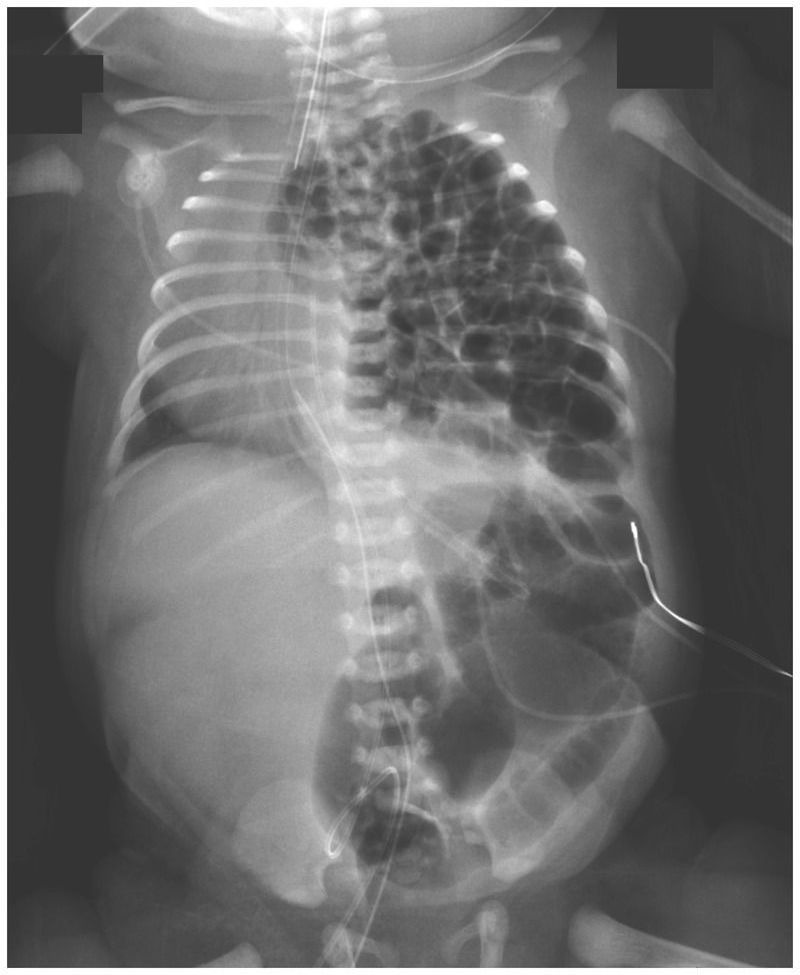

A female infant was delivered by planned cesarean section at 36 weeks of gestation because of a prenatal diagnosis of congenital diaphragmatic hernia. The neonate was intubated immediately after delivery. A nasogastric tube was inserted and suction begun to decompress the bowels to allow for better lung expansion. Chest radiography revealed multiple loops of bowel occupying the left hemithorax, which shifted the cardiothymic structures to the right. Congenital diaphragmatic hernia occurs when the diaphragm muscle fails to close during fetal development; the defect can occur on the right side, left side, or, on rare occasions, both sides. Defects on the right side, which manifest with the liver in the chest, are treated with diaphragmatic patch repair and are associated with higher rates of high-frequency ventilation, extracorporeal membrane oxygenation, and death than are defects on the left side. In our patient, the posterolateral diaphragmatic defect, also called a Bochdalek hernia, measured 3 cm by 4 cm, and because of the more favorable location on the left side, the defect was fixed surgically by primary repair on the third day of life. After the surgery, the patient received high-frequency ventilation but not extracorporeal membrane oxygenation. She was discharged home from the neonatal intensive care unit after 1 month and did well. However, the defect recurred 6 months later, and a second operation was performed.